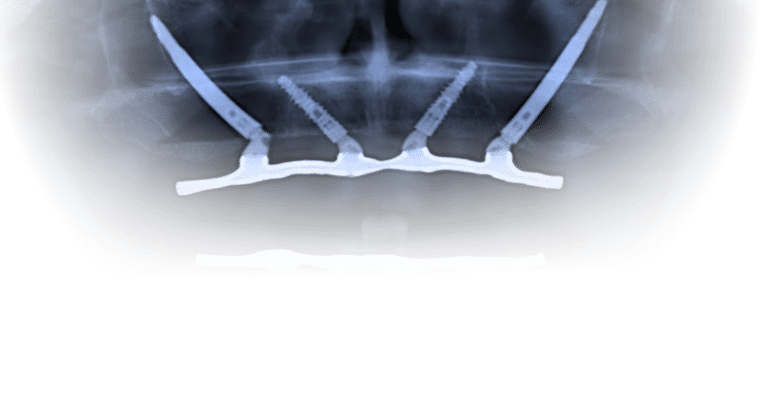

2. Cirurgia de instalação dos implantes zigomáticos

A cirurgia é realizada com todos os cuidados e conforto para o paciente. Dependendo do caso, pode ser indicada sedação consciente ou anestesia associada, para tornar o procedimento mais tranquilo.

Uma vez instalados e bem distribuídos, os implantes zigomáticos servem como pilares de sustentação para uma estrutura metálica (barra ou infraestrutura) sobre a qual será fixada a prótese.